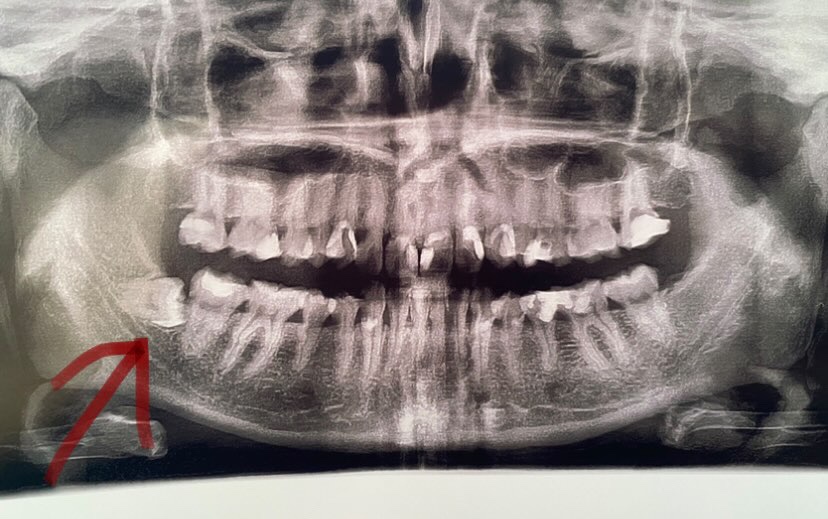

Девочки хотела поставить брекеты, на ренгене показался мудрый зуб не прорезанный, в горизонтальном направлении. Хотелось бы обойтись без удаления, у вас был такой случай что вы делали?

Без удаления никак. Он давит на соседний зуб, тот потом начнёт болеть. Вдобавок положение остальных зубов может измениться. У меня из-за зуба мудрости нижние резцы развернулись немного.

Удаляйте, мне ставили в 12 из за этих зубов, с двух сторон в таком положении, пошло смещение нижнего ряда+они давят на соседние и портят их

обязательно нужно удалить,я тоже месяц назад удалили. он будет сбоку давить на другие зубы и дальше будет искревление